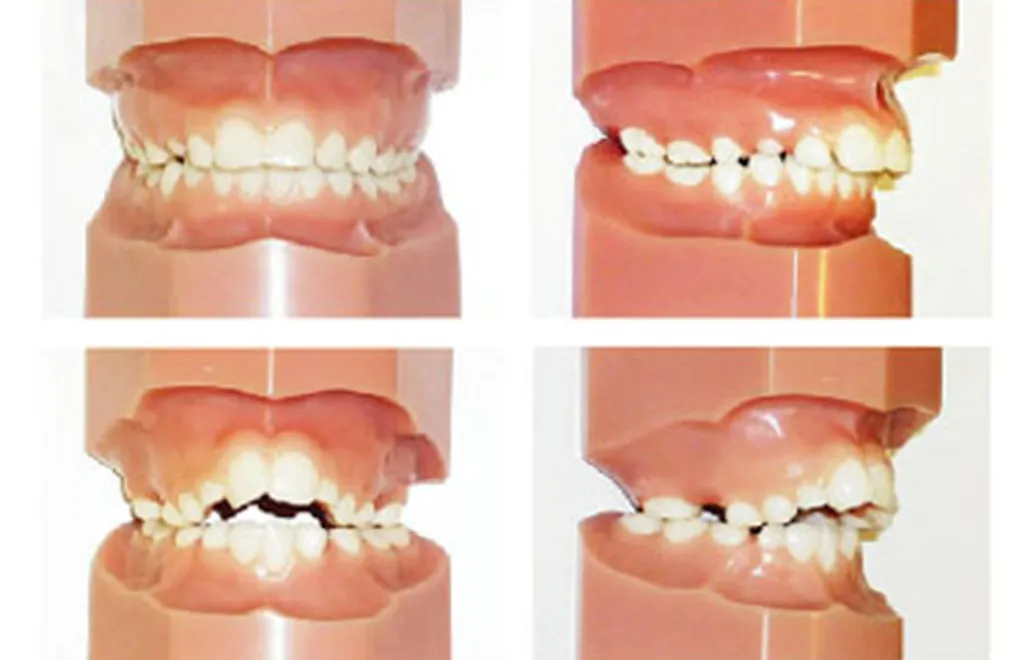

小児の不正咬合の分類

乱杭(らんぐい)歯(叢生)

顎が小さいことで歯が並ぶスペースが不足し、歯が重なり合ってでこぼこに生えています。

出っ歯(上顎前突)

上の前歯や上顎が前方に突出しています。

受け口(下顎前突・反対咬合)

下の前歯や下顎が、上の前歯よりも前方に突出しています。

開咬

奥歯を噛んでも上下の前歯が閉じず、隙間から舌が見える状態です。舌癖が影響していることもあります。

交叉咬合(こうさこうごう)

一部の噛み合わせが反対(下の歯が上の歯より前に出る)になっており、上下の前歯の中心がずれている場合もあります。その影響で、下の横の歯や下顎が前に出て見えることがあります。

過蓋咬合(かがいこうごう)

上の前歯が下の前歯を深く覆い、下の前歯がほとんど見えない状態です。出っ歯の方に多く見られる状態です。